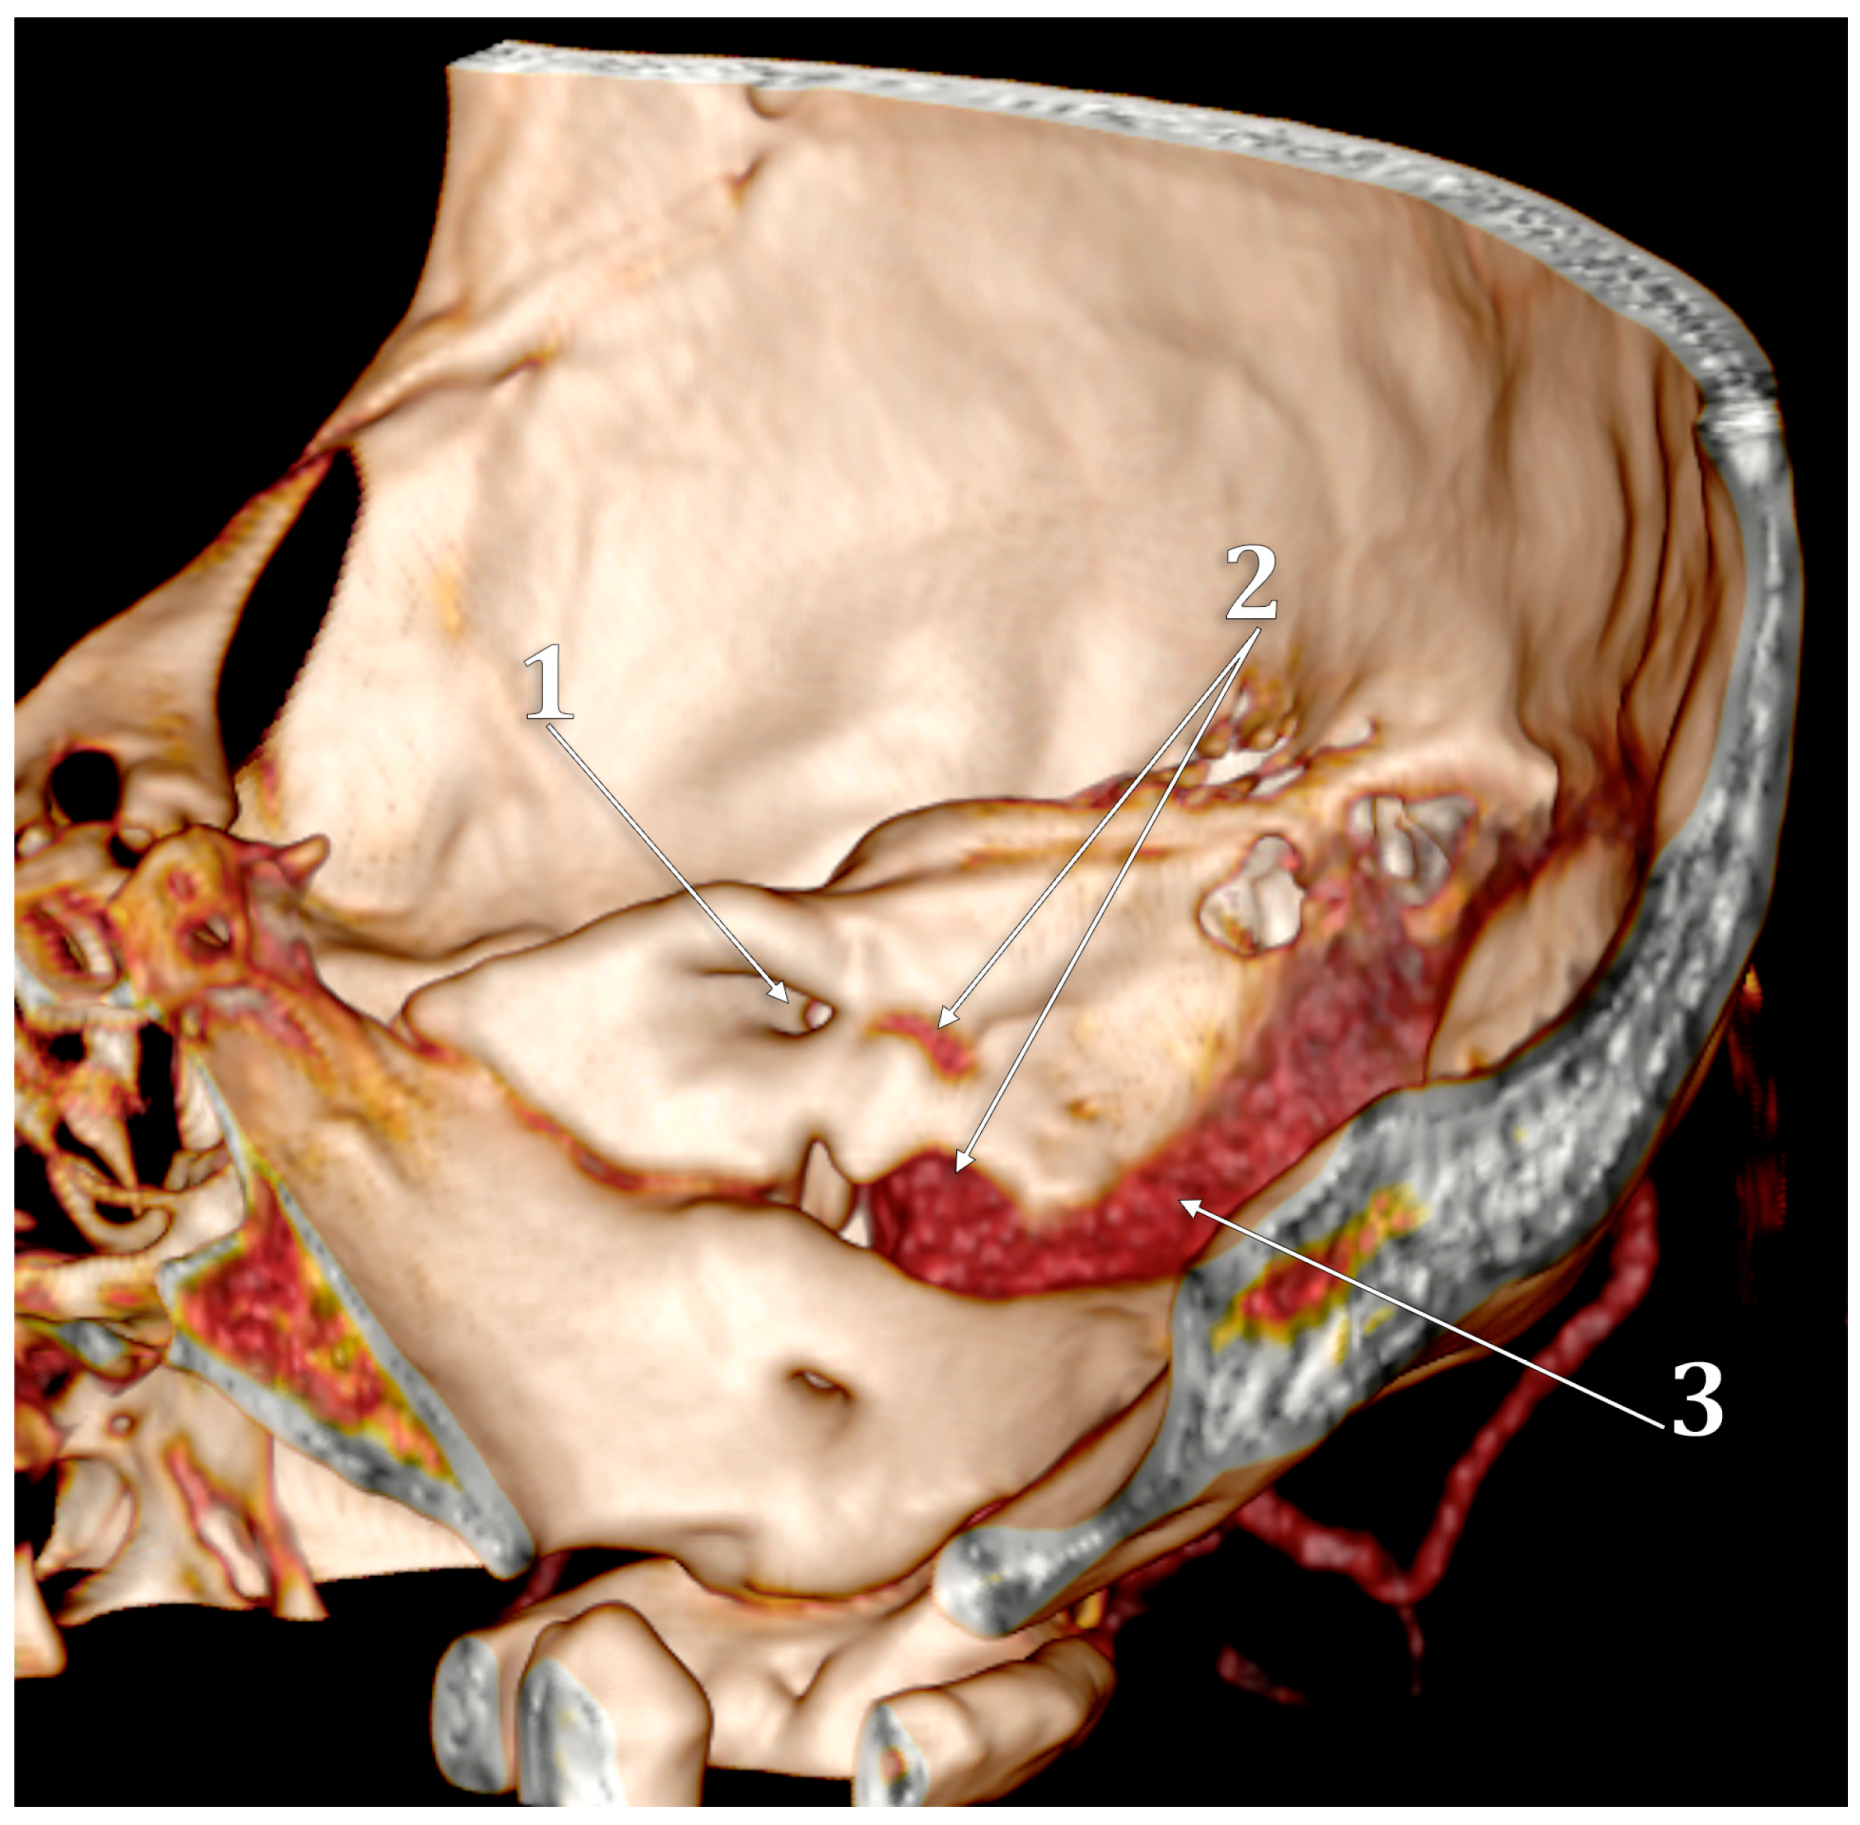

The “Condylar Jugular Diverticulum”: True or False?

- Raghuram, K.; Cure, J.K.; Harnsberger, H.R. Condylar jugular diverticulum. J. Comput. Assist. Tomogr. 2009, 33, 309–311. [Google Scholar] [CrossRef]

- Jagtap, R.; Wazzan, T.; Hansen, M.; Kashtwari, D. Condylar jugular diverticulum: A report of 3 cases. Imaging Sci. Dent. 2019, 49, 251–256. [Google Scholar] [CrossRef]

- Parillo, M.; Vaccarino, F.; Mallio, C.A.; Quattrocchi, C.C. Right Condylar Jugular Diverticulum: Contrast-enhanced Computed Tomography Findings of a Rare Anatomical Variant of Jugular Bulb. Indian J. Otolaryngol. Head Neck Surg. 2023, 75, 2257–2259. [Google Scholar] [CrossRef] [PubMed]